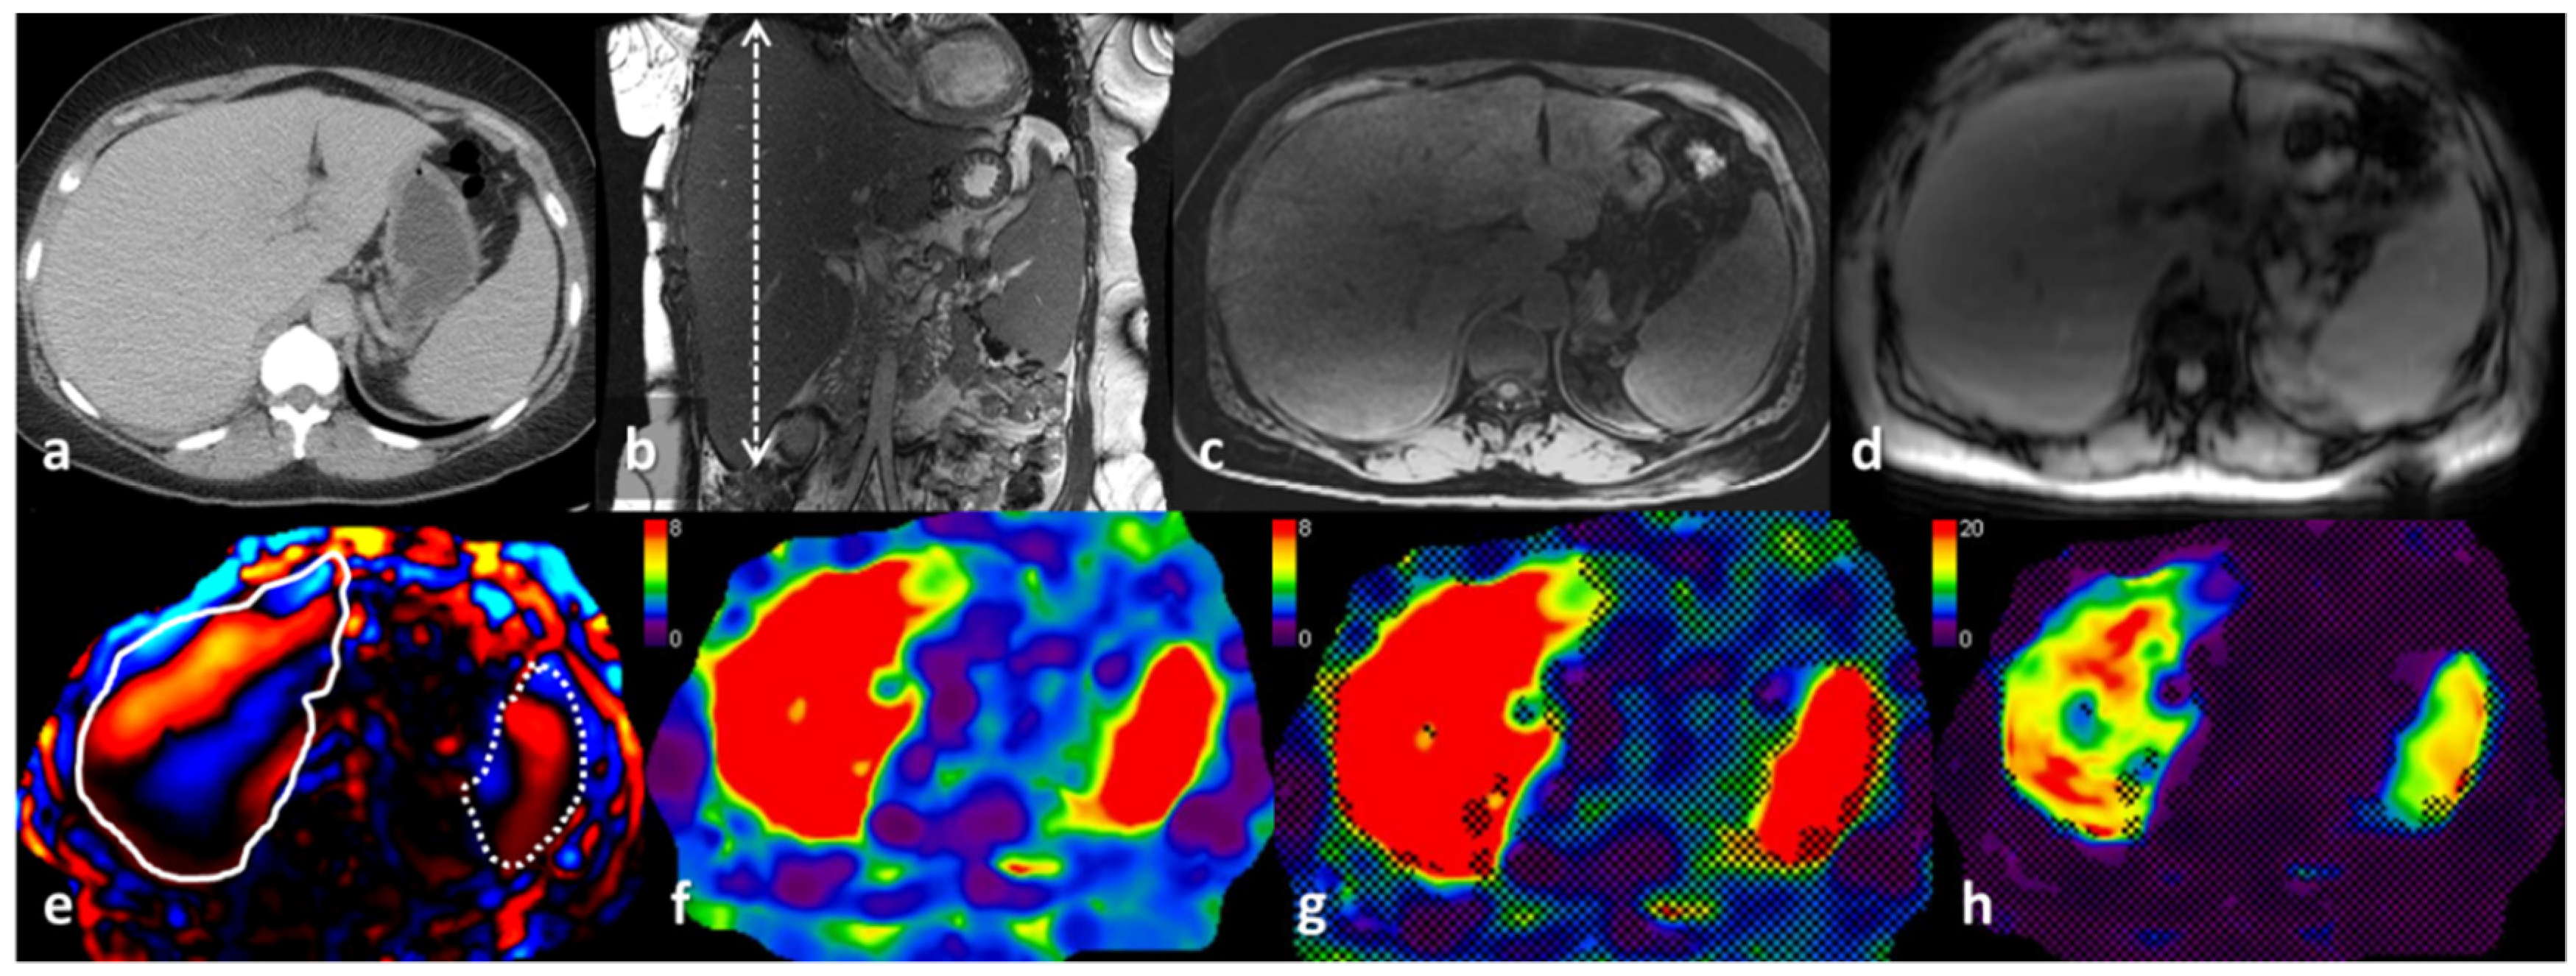

- Srinivasan, S.; Tan, Y.Q.; Teh, H.S.; Lee, P.J.; Khoo, R.N. Primary hepatic amyloidosis presenting as nodular masses on the background of diffuse infiltration and extreme liver stiffness on MR elastography. J. Gastrointestin. Liver Dis. 2014, 23, 437–440. [Google Scholar]

- Trifanov, D.S.; Dhyani, M.; Bledsoe, J.R.; Misdraji, J.; Bhan, A.K.; Chung, R.T.; Samir, A.E. Amyloidosis of the liver on shear wave elastography: Case report and review of literature. Abdom. Imaging 2015, 40, 3078–3083. [Google Scholar] [CrossRef] [PubMed]

- Matsuda, S.; Motosugi, U.; Kato, R.; Muraoka, M.; Suzuki, Y.; Sato, M.; Shindo, K.; Nakayama, Y.; Inoue, T.; Maekawa, S.; et al. Hepatic Amyloidosis with an Extremely High Stiffness Value on Magnetic Resonance Elastography. Magn. Reson. Med. Sci. 2016, 15, 251–252. [Google Scholar] [CrossRef]